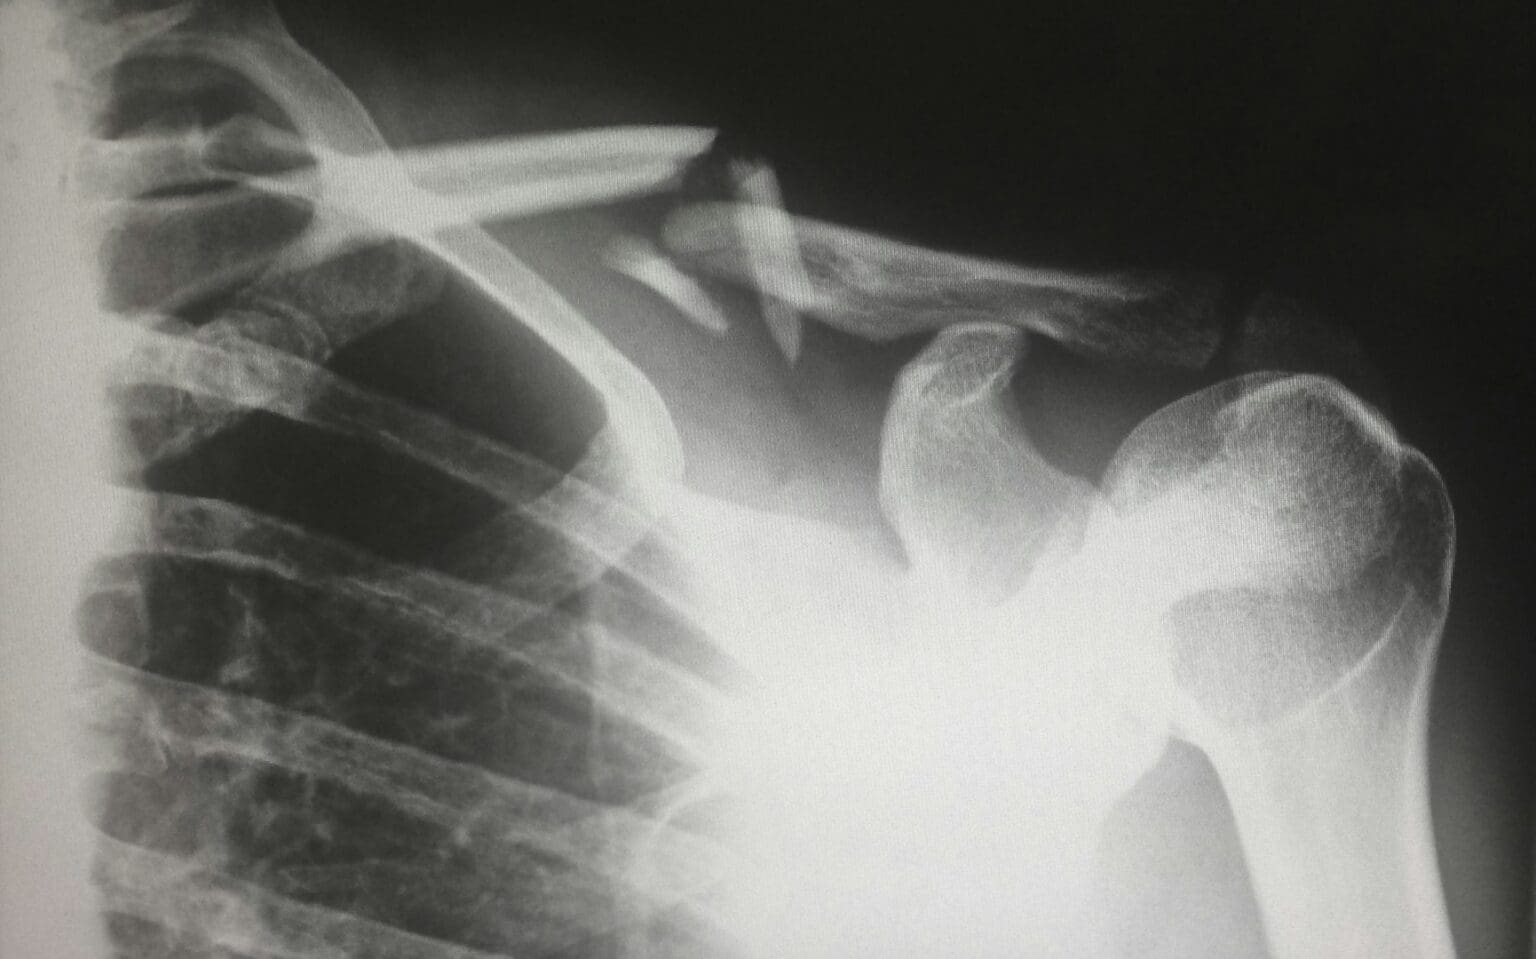

Od doby, kdy Bruce Willis hrál ve filmu Vyvolený, příběhu superhrdiny, který přežije řadu smrtelných nehod a setká se se svým „protivníkem“, kterého hraje Samuel L. Jackson a který trpí osteogenesis imperfecta (nemocí křehkých kostí), je tato nemoc veřejně uznávána. Není tedy divu, že někoho napadne sklo jako náhrada kostí.

Sklo i kost mají díky své molekulární struktuře společnou klíčovou vlastnost: lépe odolávají stlačení než natažení. Tato vlastnost je základem oxidu křemičitého, hlavní složky skla, která při vysokých teplotách přechází do kapalného stavu a lze ji tvarovat. Díky tomu je možné vytvářet implantáty, které lze vyrobit tak, aby dokonale zapadly do poškozených částí kosti. I když má sklo potenciál, zdokonalení procesu tisku bylo překážkou. Zatím

Tým čínských vědců vyvinul 3D tisknutelné bioaktivní sklo s pružností podobnou kosti. Ve studii publikované v časopise ACS Nano autoři ukazují, že v testech na zvířatech toto sklo podporovalo růst kostních buněk déle než obyčejné sklo a téměř se vyrovnalo přednímu materiálu pro zubní implantáty.

Autoři pod vedením Huanana Wanga hledali čistší řešení. Zkombinovali opačně nabité částice oxidu křemičitého s vápenatými a fosfátovými ionty, o nichž je známo, že vyvolávají tvorbu buněk. Tato směs vytvořila tisknutelný gel, který mohl tvrdnout při teplotě kolem 700 °C. Tým porovnal své nové biosklo, obyčejné křemičité sklo a komerční zubní kostní náhradu při opravě králičí lebky.

Zatímco komerční produkt stimuloval rychlejší počáteční růst, biosklo se ukázalo být odolnější. Po osmi týdnech se většina kostních buněk přichytila ke kostře z bioskla, zatímco u obyčejného skla byl růst malý nebo žádný. Studie uvádí, že jejich materiál udržel růst kosti déle než stávající možnosti. Svou práci označili za průlom v oblasti cenově dostupných, přizpůsobitelných kostních náhrad s využitím daleko za hranicemi stomatologie.